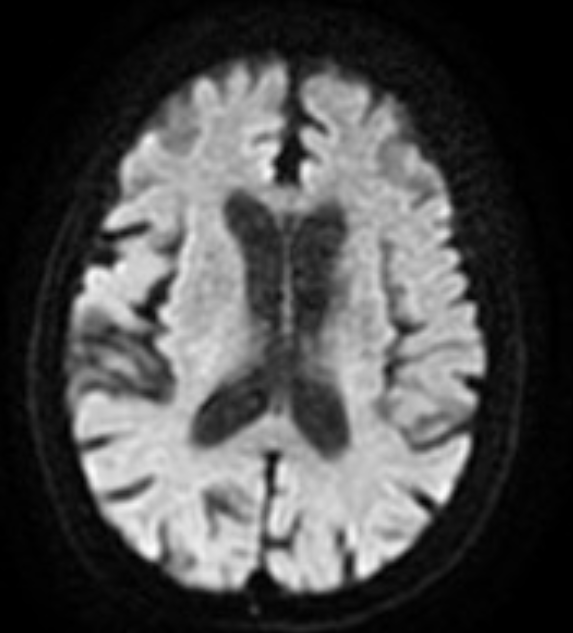

麻醉苏醒后,家属欣喜地发现老人已能模糊发出简单音节,原本无法动弹的右手也可微微抬起。术后24小时复查头颅CT,未出现出血等并发症;术后第三天颅脑MRI+DWI检查提示,缺血脑组织得到有效挽救,仅残留非核心区腔隙性梗死,为后续康复奠定了坚实基础。

术后3天复查颅脑MRI+DWI。